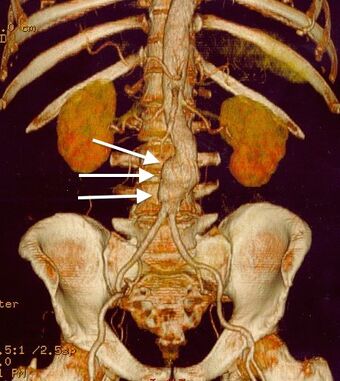

| CT reconstruction image of an abdominal aortic aneurysm (white arrows) |